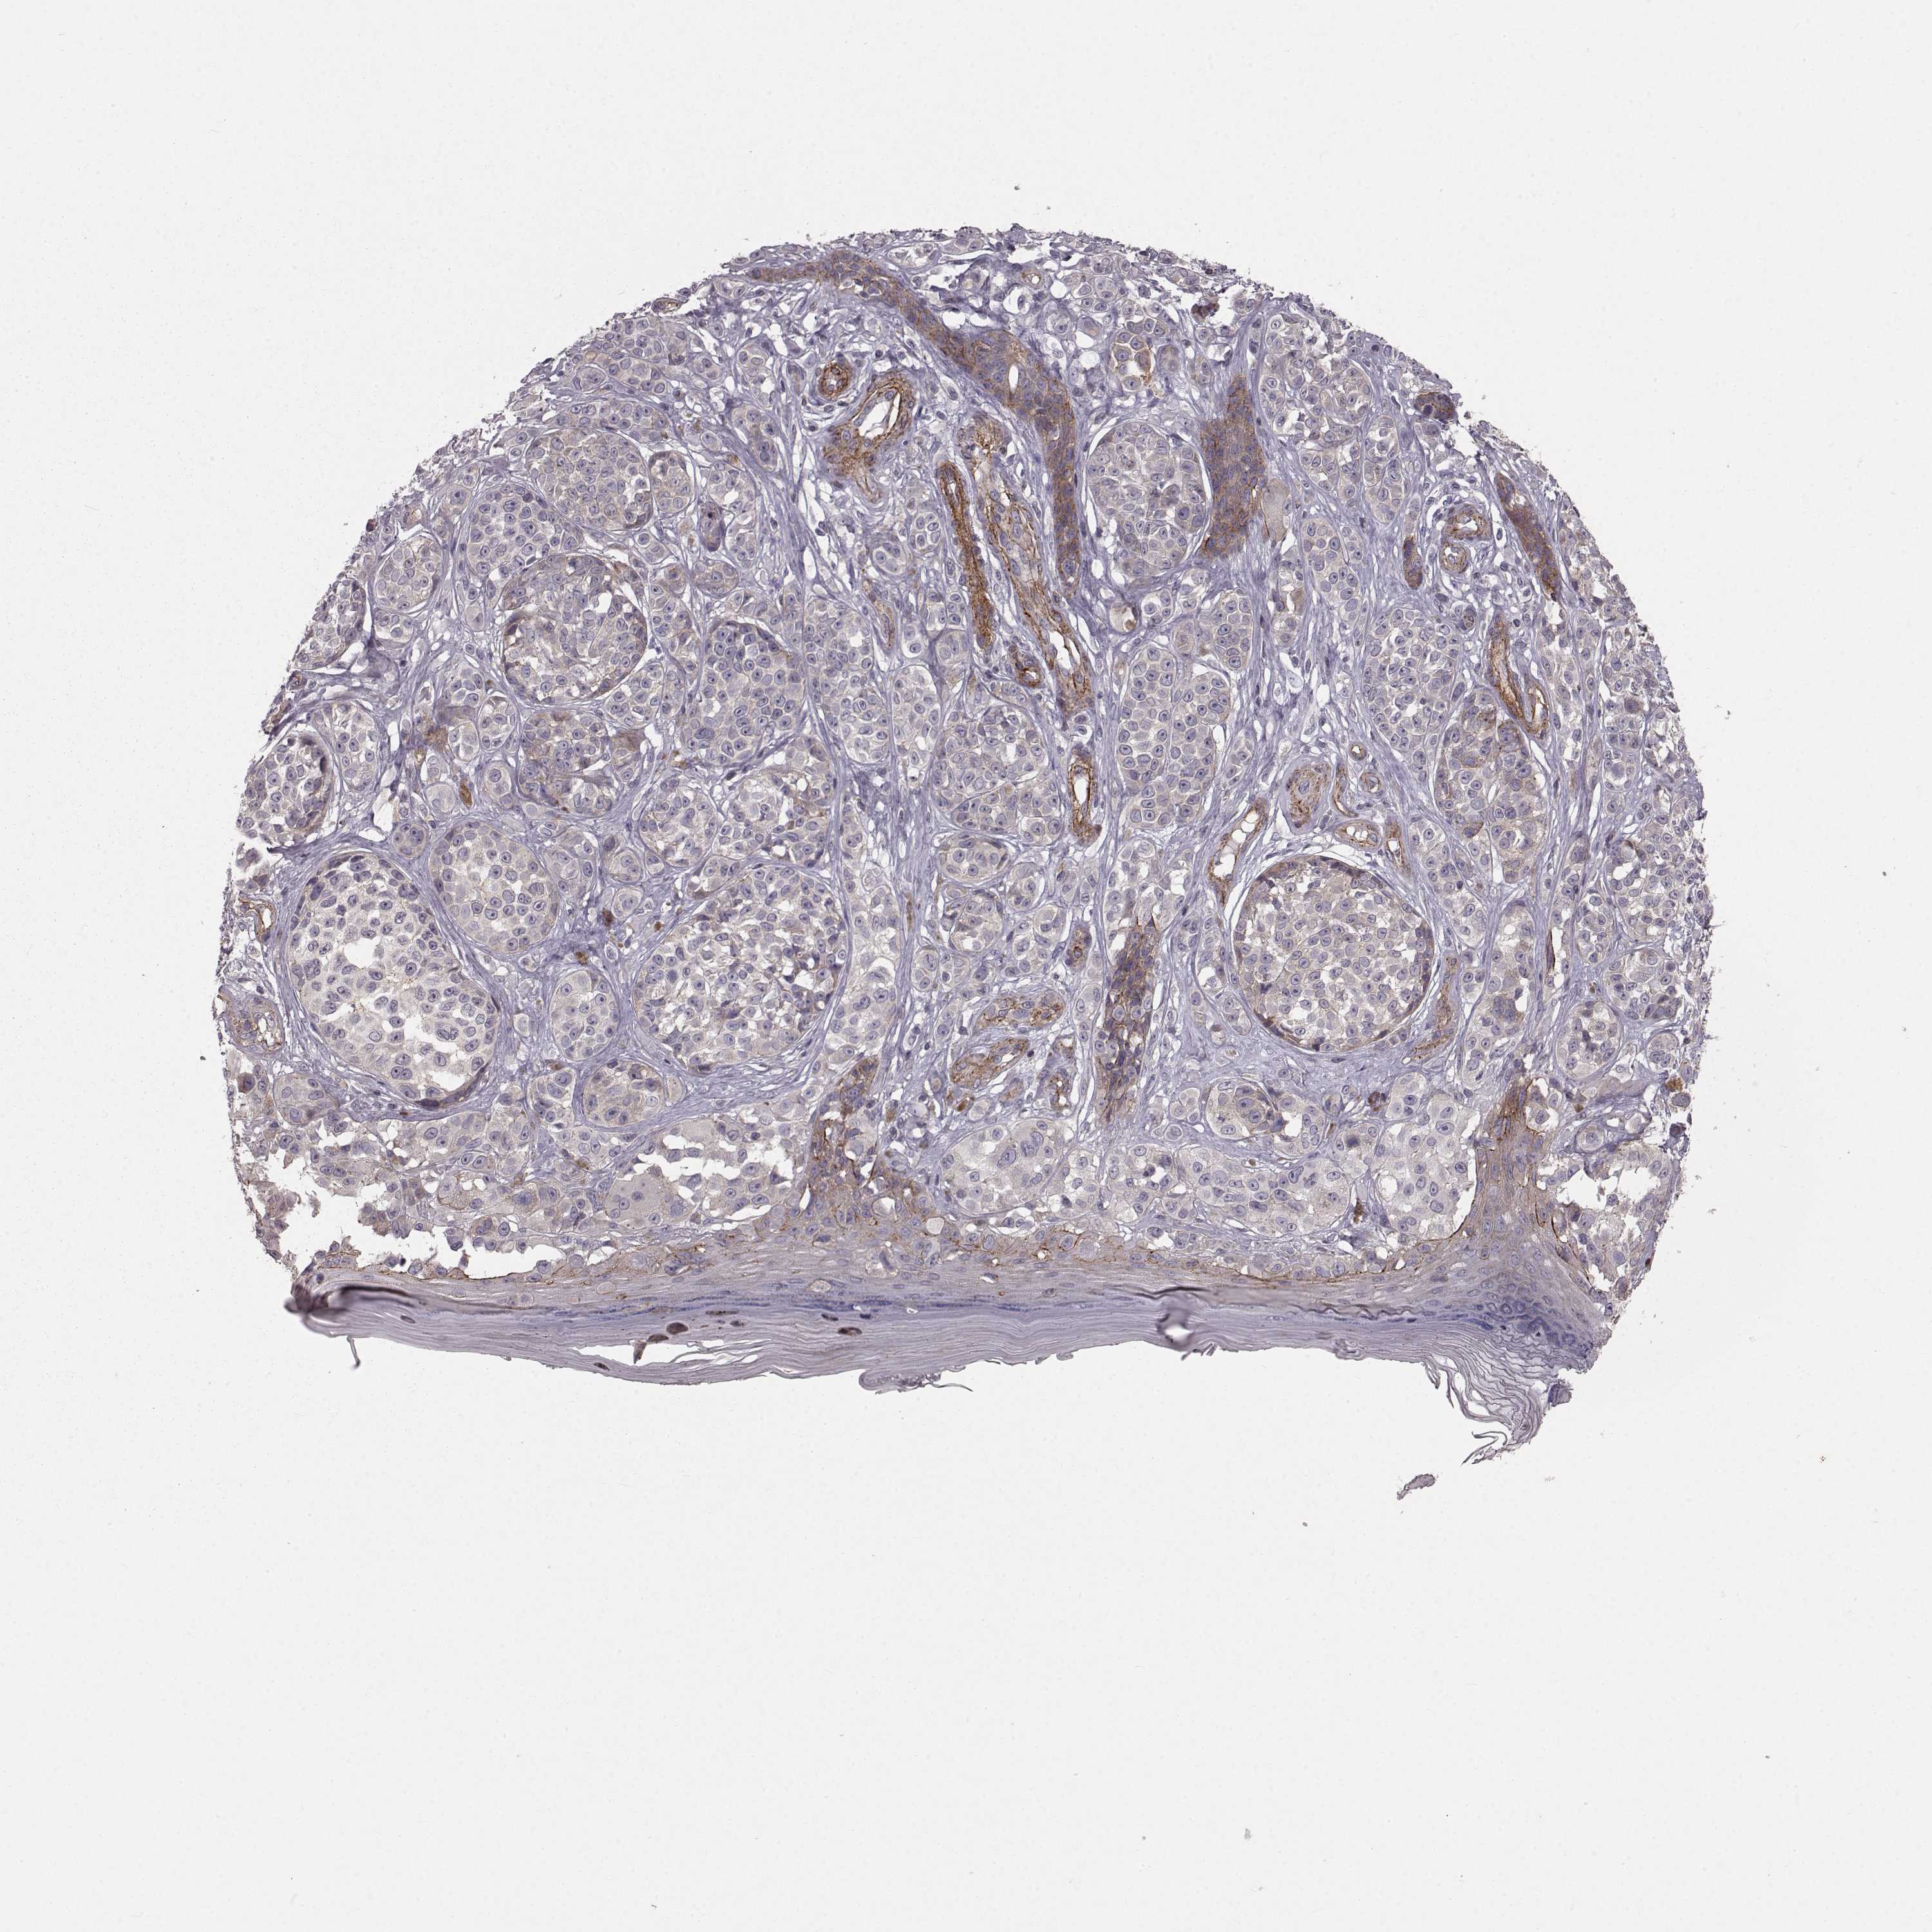

MELANOMA - Protein expressioni

A mouse-over function shows sample information and annotation data. Click on an image to view it in a full screen mode. Samples can be filtered based on level of antibody staining by selecting one or several of the following categories: high, medium, low and not detected. The assay and annotation is described here.

Note that samples used for immunohistochemistry by the Human Protein Atlas do not correspond to samples in the TCGA dataset.

Antibody stainingi

Antibody staining in the annotated cell types in the current human tissue is reported as not detected, low, medium, or high, based on conventional immunohistochemistry profiling in selected tissues. This score is based on the combination of the staining intensity and fraction of stained cells.

Each image is clickable and will lead to virtual microscopy that enables deeper exploration of all samples and also displays staining intensity scores, fraction scores and subcellular localization as well as patient and tissue information for each sample.

Antibody HPA067812

Antibody HPA071461

Staining

High

Medium

Low

Not detected

Intensity

Strong

Moderate

Weak

Negative

Quantity

>75%

75%-25%

<25%

None

Location

Nuclear

Cytoplasmic/membranous

Cytoplasmic/membranous,nuclear

Malignant melanoma, NOS

Malignant melanoma, Metastatic site